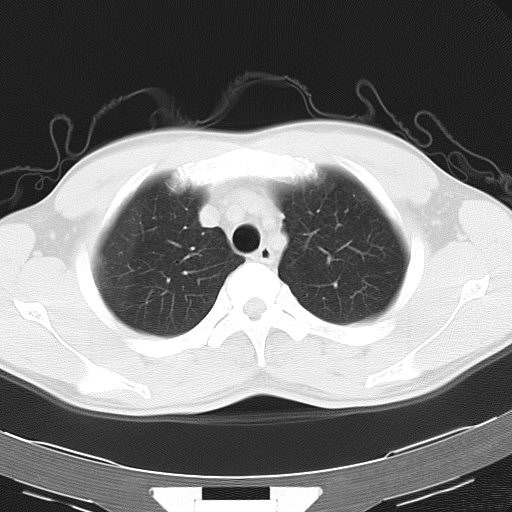

男,34岁,咳嗽2~3个月,无咳血,病初有发热。

两上肺磨玻璃样改变,均位于肺外周,考虑1、肺泡蛋白沉着症?2、肺泡炎?请询问有无养鸟史 3、脱屑性间质性肺炎?建议进一步检查、复查随访

两上肺的ggo,靠近胸膜,不是以节段分布,青年男性,个人意见为吸入性的真菌感染可能为大------------呼吸内科医生

两肺上叶近胸膜磨玻璃样阴影,考虑1、炎性病变。 。2、过敏性炎症?

病灶特点:

分布在肺野的外带,病灶边缘清楚,病灶以磨玻璃影为主夹杂少许纤维状高密度影

支持zhangzhongshou主任,考虑蛋白沉着症可能性大

再仔细阅读该病人的ct片,我们不难发现,病例所表现的正是外围型的肺泡蛋白沉积症表现,即:为多发性条片状、斑片状及斑块状高密度影,弥散、对称或不对称分布于两肺或一侧肺外围部位。病变区与正常肺组织及脏层胸膜面分界清晰,呈地图样改变。